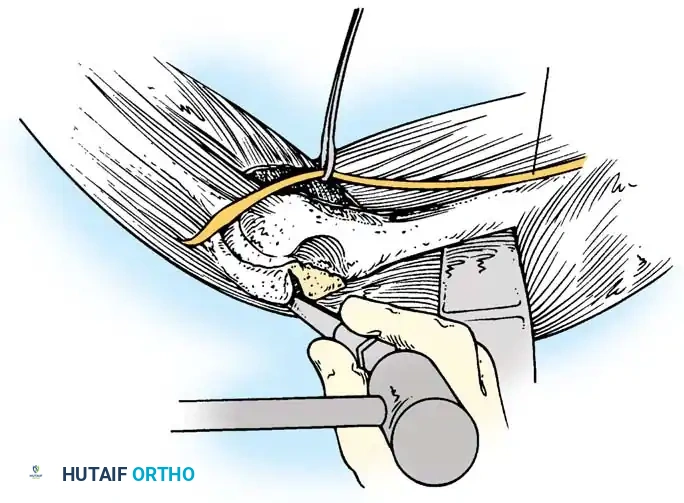

Intraarticular Cruciate Ligament Reconstruction

Arafiles described the creation of an intraarticular "cruciate" ligament using tendon grafts to stabilize the joint while allowing flexion-extension exercises as early as 6 days postoperatively.

Fig. 58-24 A and B, Slot in trochlea and drill holes showing the course of the tendon graft. C and D, Completed repair acting as an intraarticular cruciate ligament. (From Arafiles RP: Neglected posterior dislocation of the elbow, J Bone Joint Surg 69B:199, 1987.)